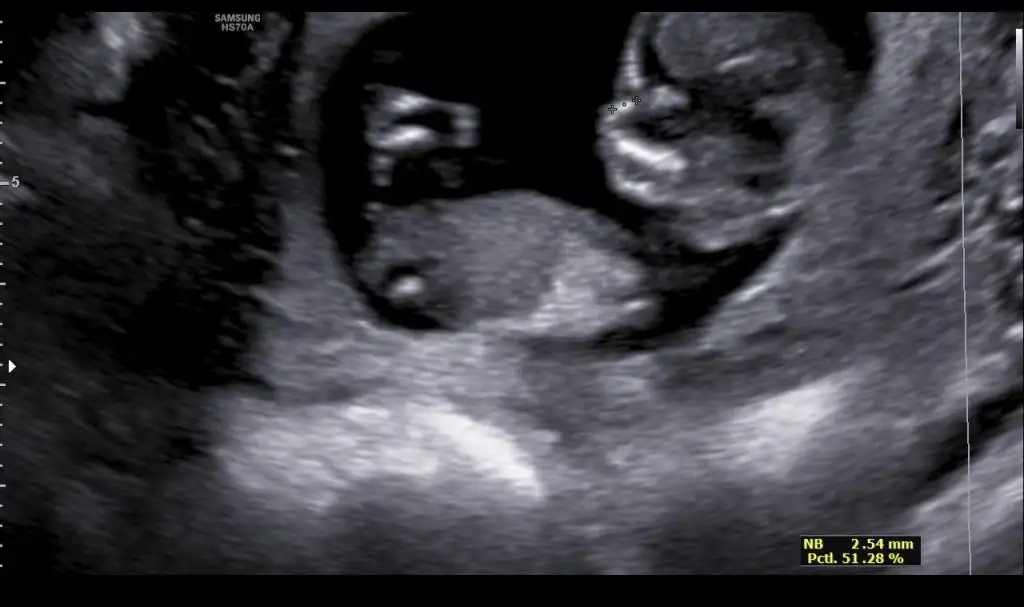

Merhabalarr bana 10 gün önce kız gibi ama tekrar yollayın demiştinizzz doktorumuz 2 hafta sonra söyleyecek şuan 12+1iz tekrar bakarsanız sevinirimm

Eklentiler

• 29DE1470-05FA-4EB9-9560-004FA22A4819.webp

29,9 KB · Görüntüleme: 65

• FB329B02-32D0-4C1D-B2AF-9F18D864BBD1.webp

24 KB · Görüntüleme: 82